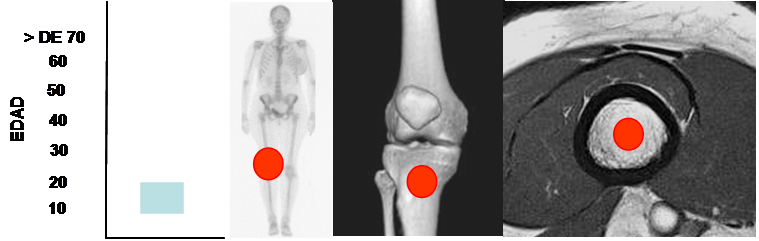

Fig 98. Fibroma no osificante.

Mayor frecuencia en la 2º década. Predominio en la rodilla.

Lesión metafisiaria, de ubicación central.